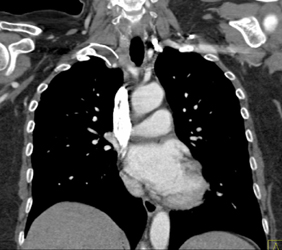

Thyroid Cancer Invades the Right Subclavian and Carotid Aa